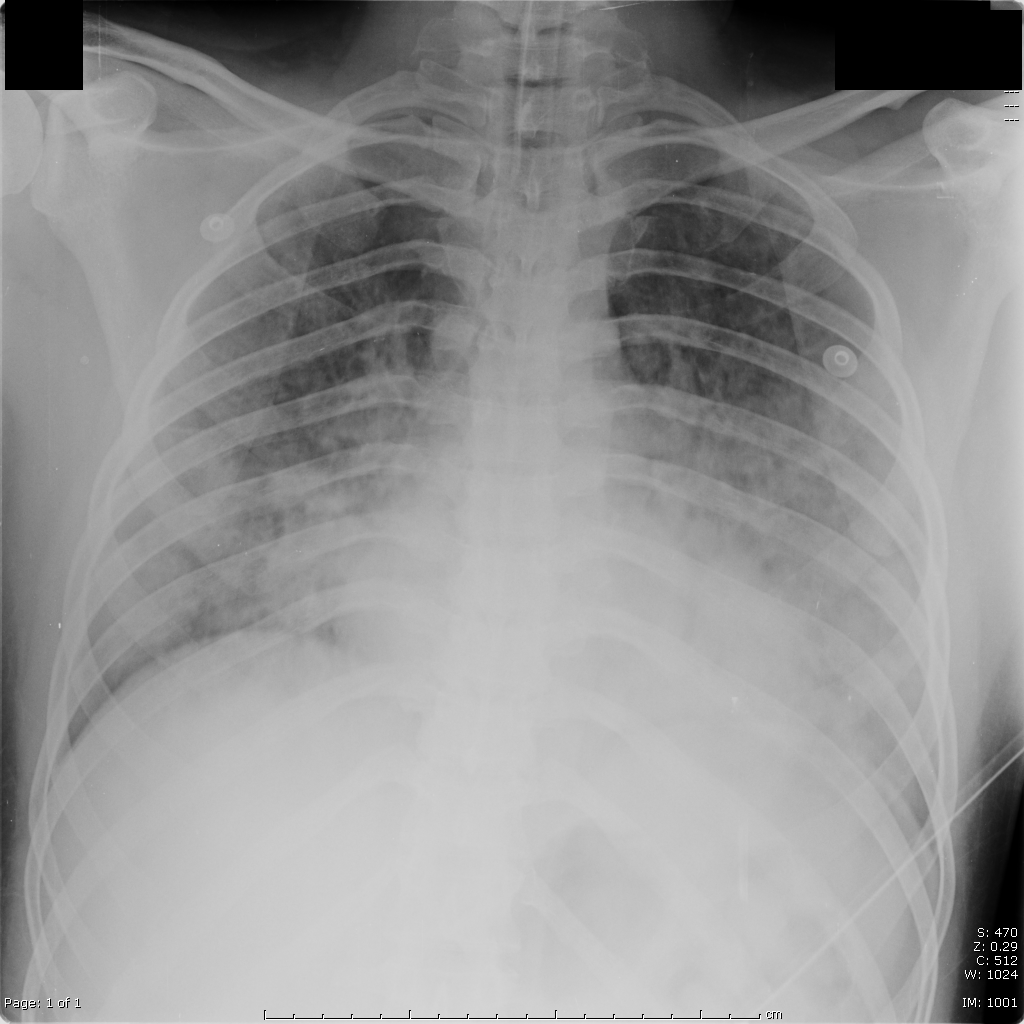

Bilateral symmetric alveolar opacities located centrally in mid and lower lung zones are typical, often in a "bat wing" distribution

.bmp)